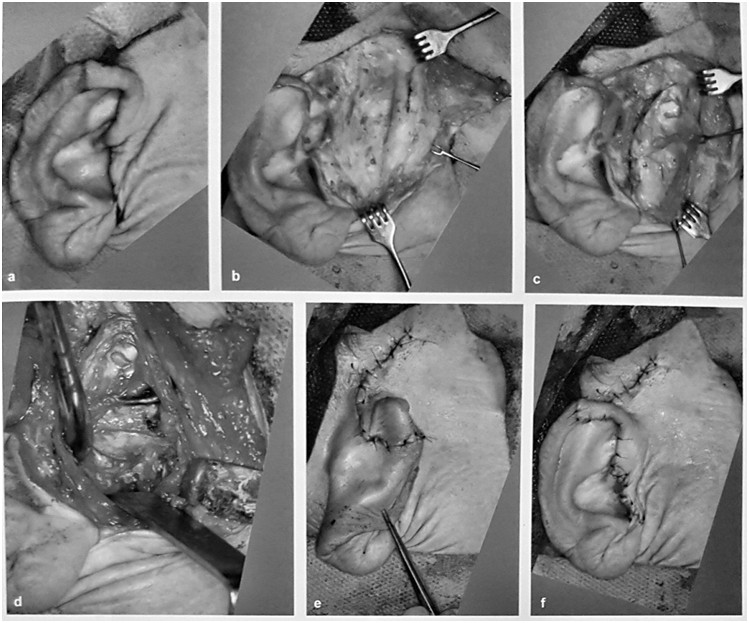

Na rycinie przedstawiono jeden z uniwersalnych dostępów chirurgicznych do wyrostka kłykciowego. Jest to dostęp: